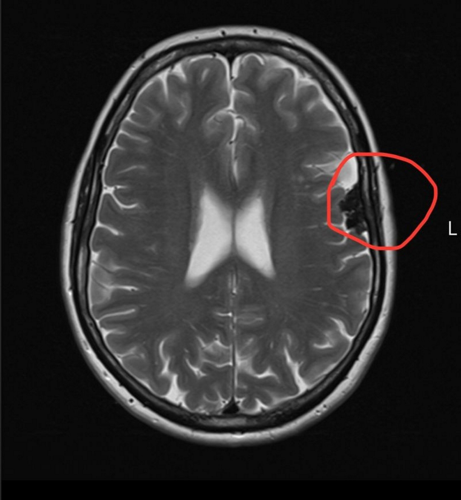

A woman who blamed her brain fog on the menopause and long work hours was diagnosed with two brain tumors.

A late night MRI revealed a meningioma, a type of brain tumor, and five months later, after waiting for specialists to get back to her, she was told she had two brain tumors.

The tumors are now being monitored with regular MRI's.

Doctors advised Elizabeth to “watch and wait,” as both tumors were benign and slow growing, but she will now need regular MRI scans to monitor the growth.